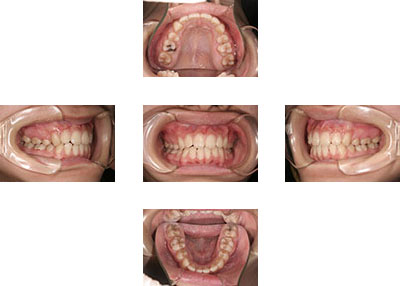

咬み合わせがよくなった症例

- 術前

- 術後

20歳で八重歯を治したいと言って来院されました。でも前歯は全く咬み合っていない状態でしたので、相談を重ね治療を始めることにしました。外科手術も併用することも相談しましたが、手術はしたくないとのことでしたので、透明なブラケット、ヘッドギア、顎間ゴムを用いて治療を始めました。上下左右の小臼歯を抜歯しています(計4本)。少し遠くから通院されていたので来院間隔が空くことも多かったのですが、4年弱できっちりとした咬合にしあがりました。